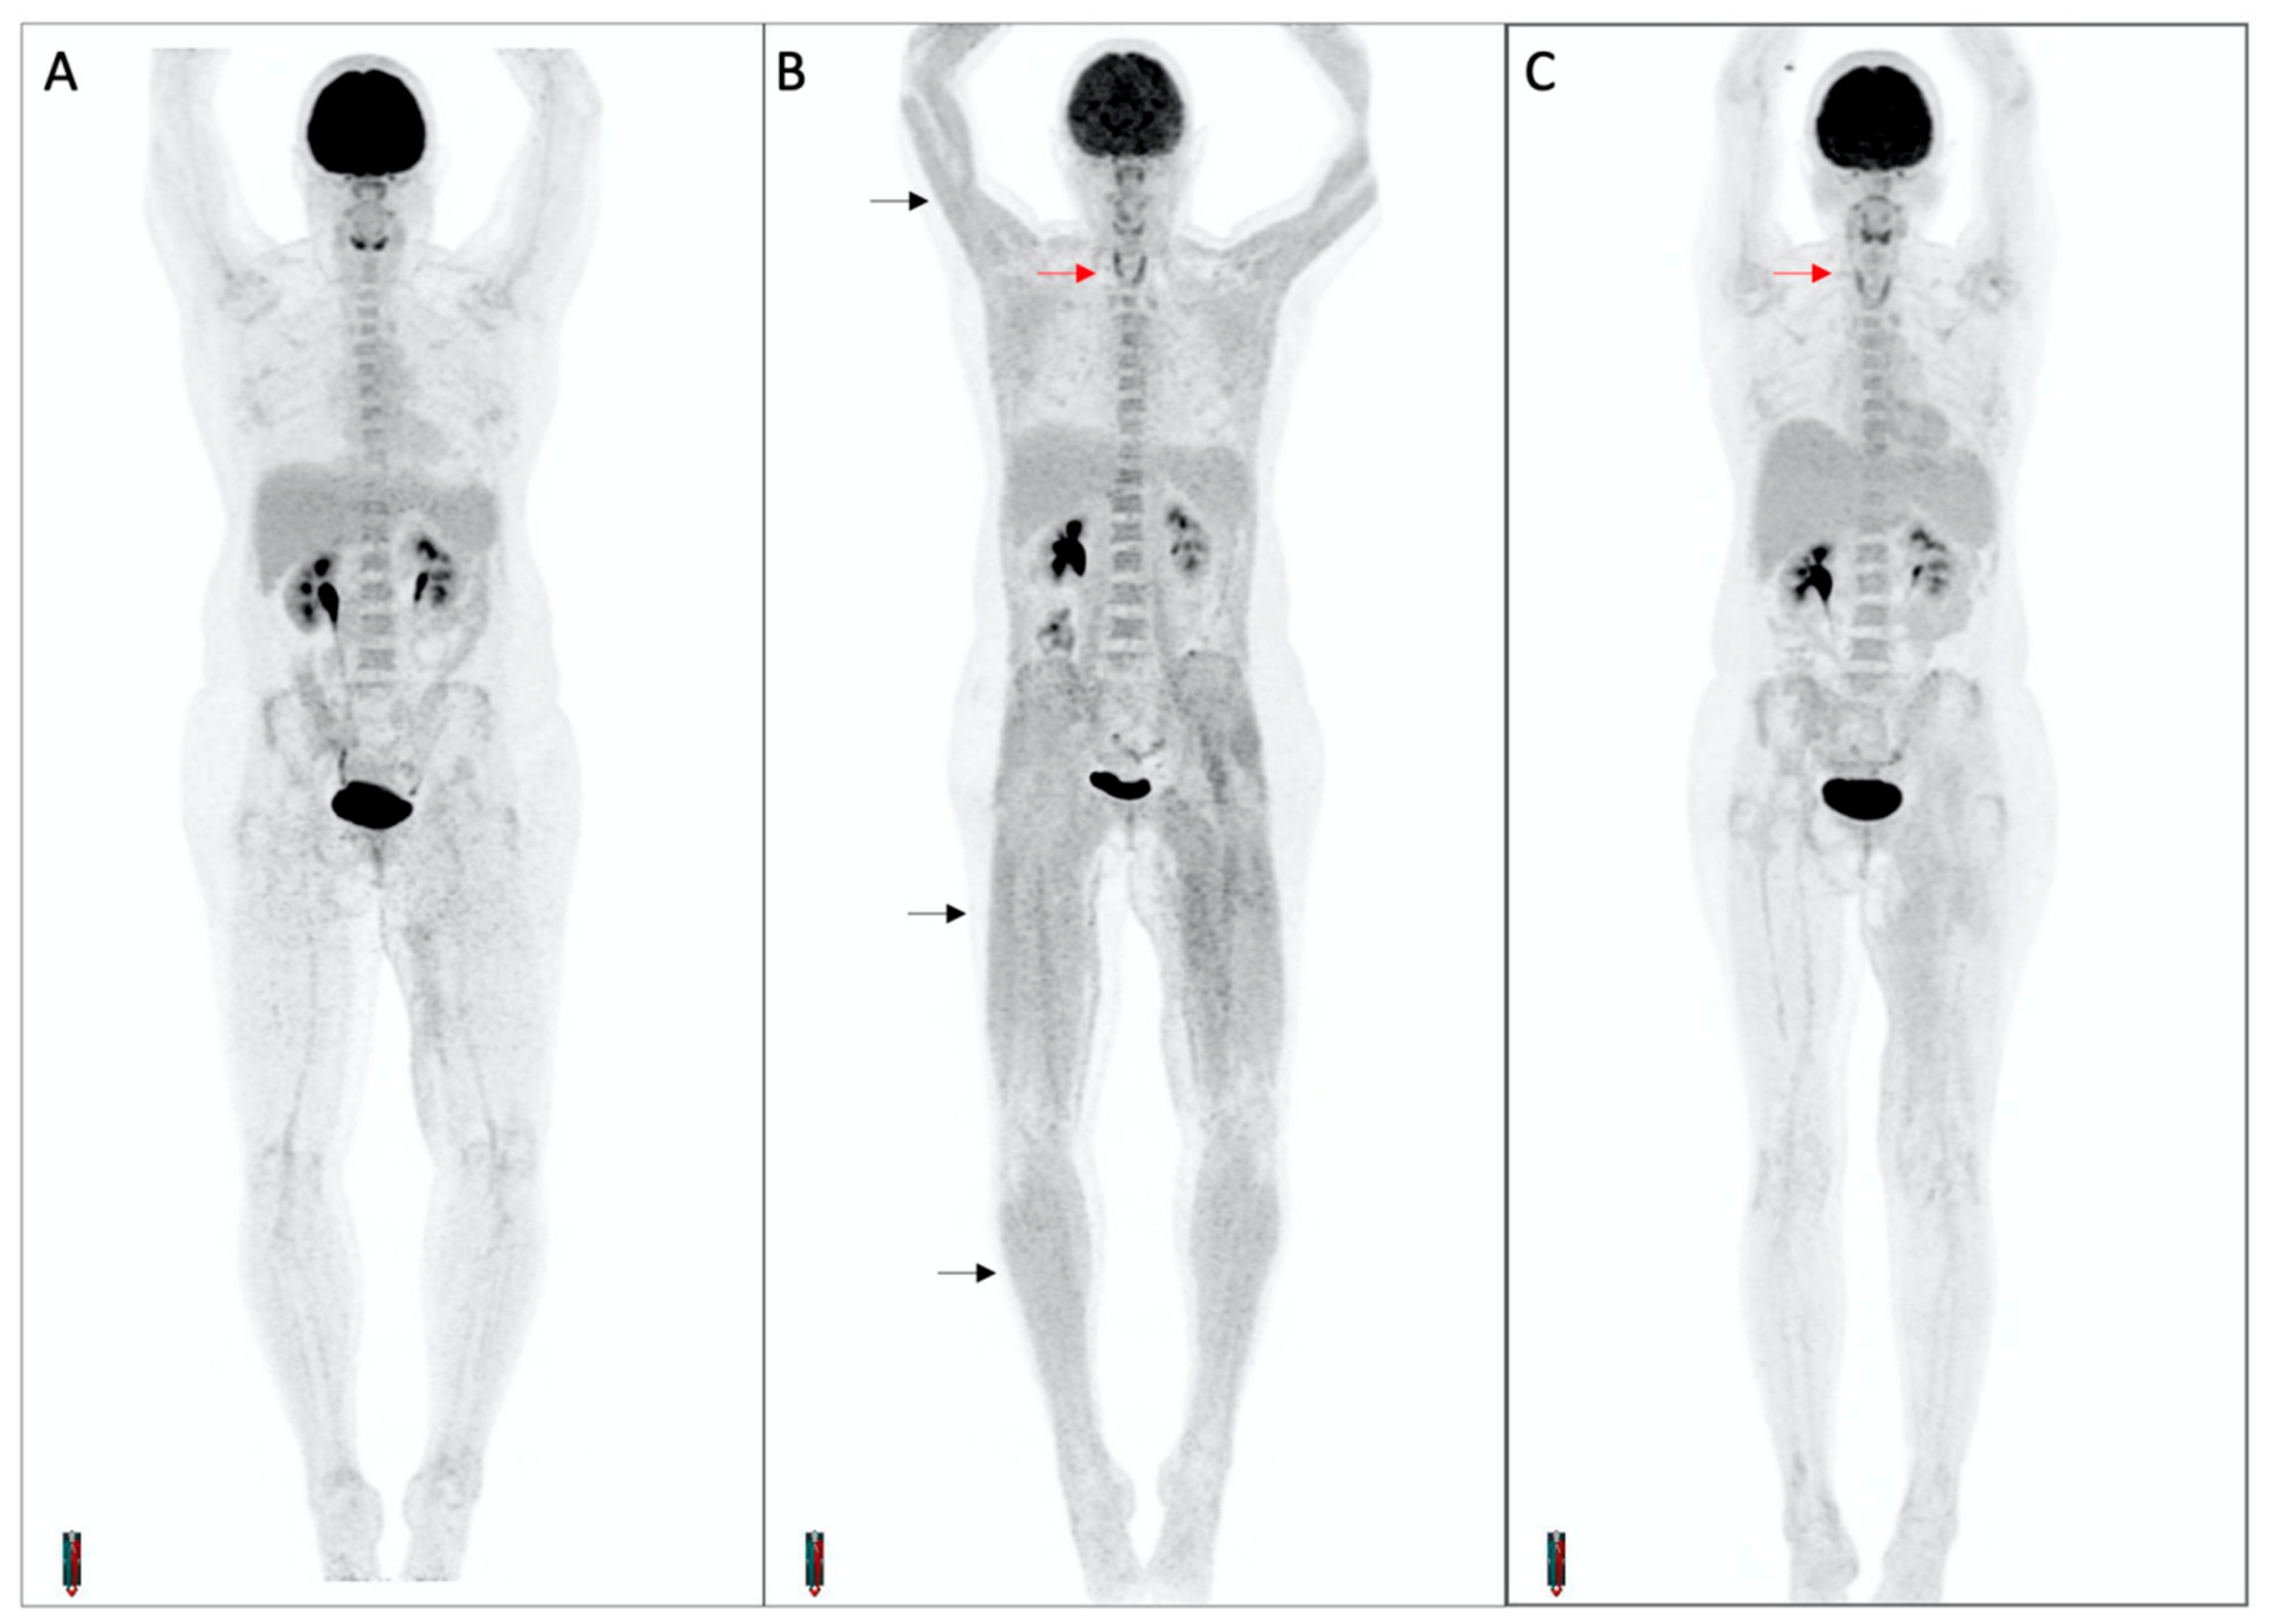

3.5. Concomitant Muscle Uptake